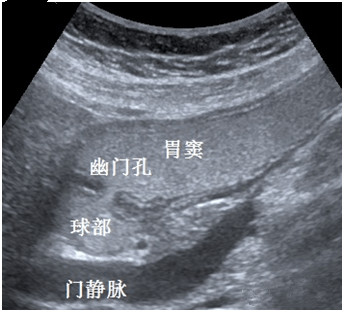

胃肠超声造影检查是采用口服造影剂充盈胃、肠腔,通过改善胃肠的超声内部环境,以利于超声波声束穿透,使胃肠结构和其病变在超声检查下更加清晰地显示,同时通过动态观察对胃肠功能作出有效评估。它是一种无创、无射线、不插管、无痛苦、安全、简便有效、可重复性强的检查方法。

目前,超声造影检查在胃肠疾病方面虽有其局限性,但作为一种简便、无创、准确性较高的客观影像学检查方法,它弥补了其他检查方法的一些不足和缺陷,适用于胃肠道疾病的筛查,尤其适用于胃肠镜禁忌症的患者。